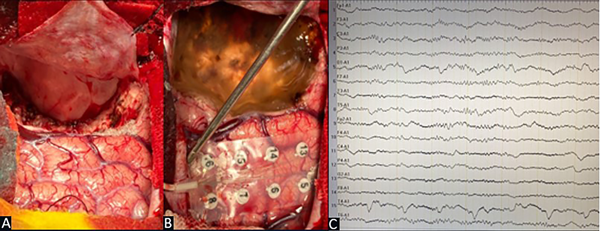

Mediante la apertura dural en H se identificó la presencia de cambios corticales a nivel frontopolar derecho. Se colocó grilla de 16 contactos en la circunvolución frontal superior y media derecha para control por EcoG con objetivación de descargas a nivel de los contactos 2-3-10 y 11 (Figura 3). Se realizó exéresis de la lesión con confirmación posterior, mediante el uso de EcoG, de la inexistencia de tejido residual epileptógeno (Figura 4).

Figura 4. Caso 1. A) Lecho quirúrgico. B) Control postresección de zona perilesional. C) EcoG postresección: resolución completa de la actividad epileptiforme.